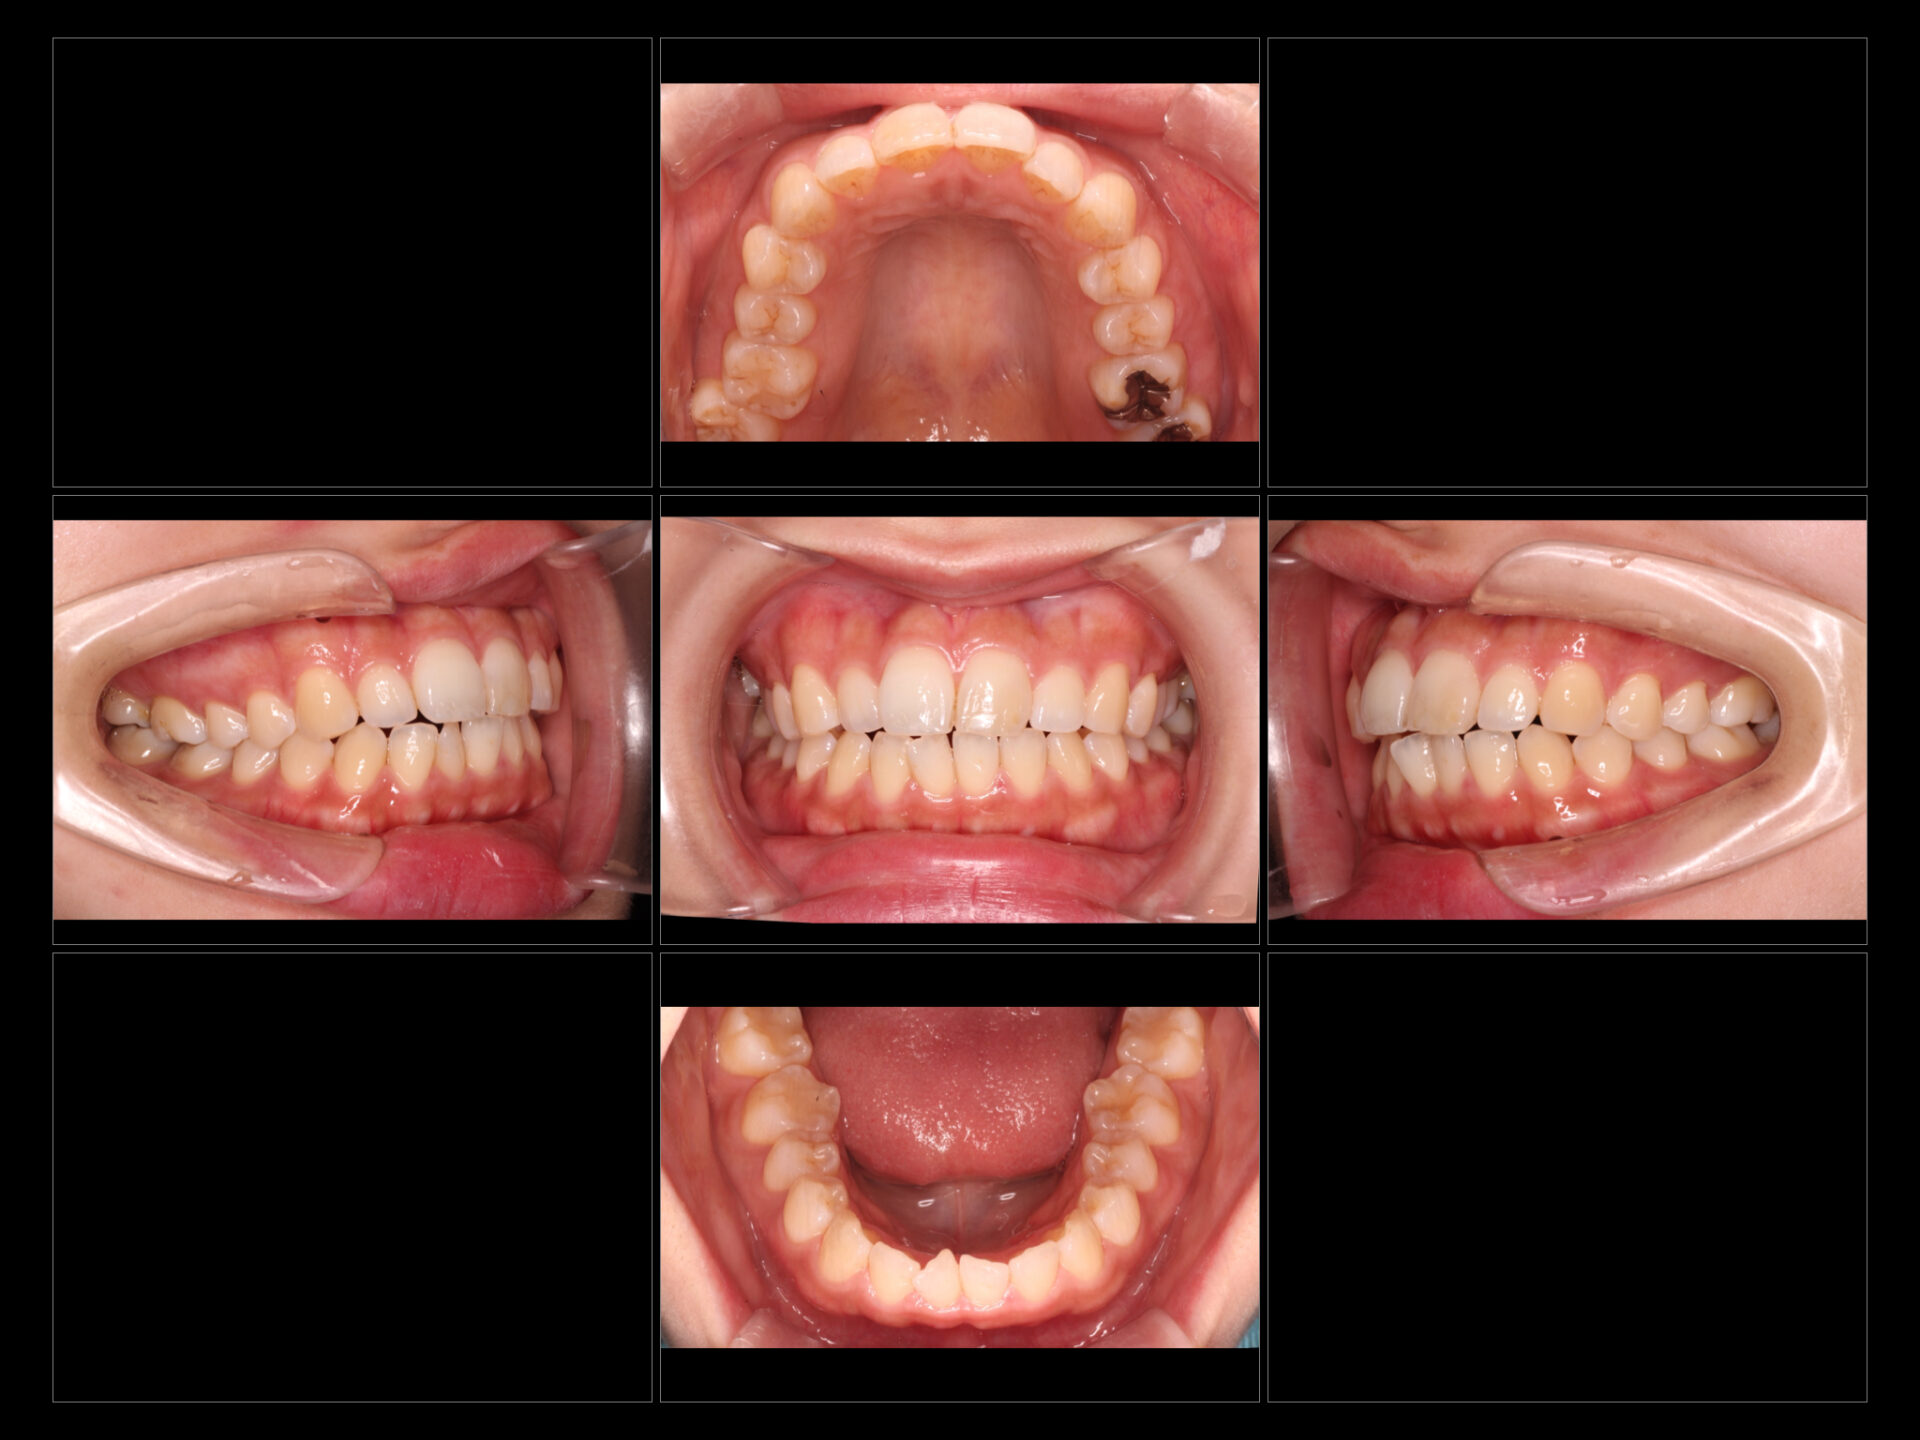

2. Before / After(画像)

3. 治療内容・結果

歯列矯正: マウスピース型矯正装置を用い、1年という期間でスムーズに歯並びを整えました。

ホワイトニング: 矯正治療の進捗に合わせ、ホワイトニングを実施。歯並びだけでなく歯の色調を明るくすることで、治療完了後の満足度がより高まりました。

口元の変化: 歯並びが整ったことで、下顔面(口元)のバランスが改善され、より洗練された印象になりました。